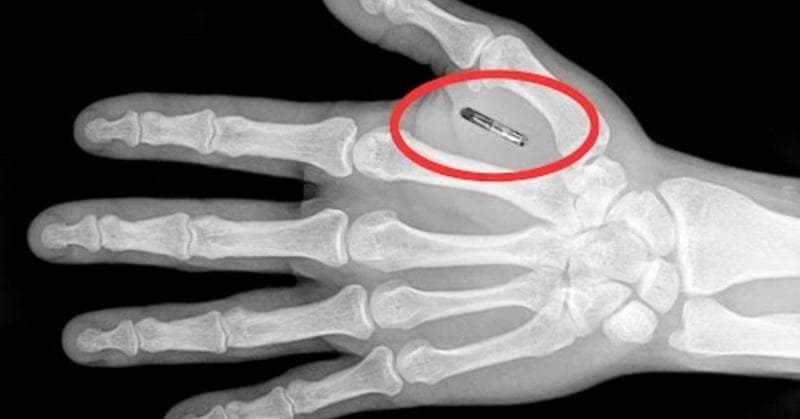

Chip kecil seukuran butiran beras ini ditanam di sela ibu jari dan telunjuk. Fungsinya sederhana tapi menggoda yaitu menggantikan kartu akses, tiket transportasi, hingga alat pembayaran kontak. selama sistem yang digunakan mendukung teknologi tersebut. Praktis, cepat, dan futuristik.

Fenomena ini mulai meledak sekitar 2014. Saat itu, puluhan ribu warga Swedia penasaran dan ingin mencoba kehidupan “tanpa dompet”. Diperkirakan 3.000 hingga 6.000 orang telah menanam chip pada masa puncaknya. Namun beberapa tahun terakhir, tren tersebut menunjukkan perlambatan. Antusiasmenya belum hilang, tetapi euforianya nggak lagi sebesar sebelumnya.